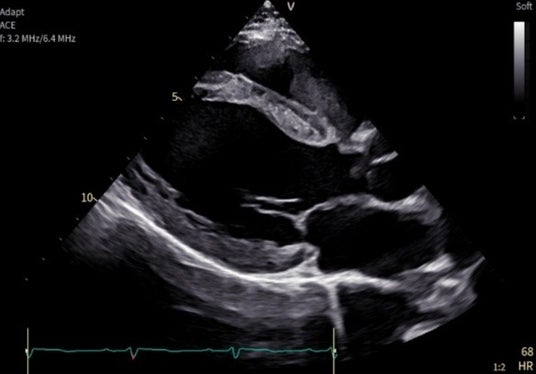

「Vivid Pioneer」は、検査室や病室など限られたスペースにも適するようコンパクトに設計され、超音波画像診断装置に最適な大型モニターも備えています。またユーザーインターフェイスもシンプルで直感的に操作できるよう刷新されました。加えて、バッテリー搭載が可能となり、電源を抜いても検査を継続することや、停電時でも最大5分間スキャンすることができます。そのほか、プローブは広帯域の周波数を使用し幅広い年齢層やさまざまな体格の患者さんに対応し、心臓の微細構造を鮮明に描出します。

広帯域の周波数を用いたプローブ